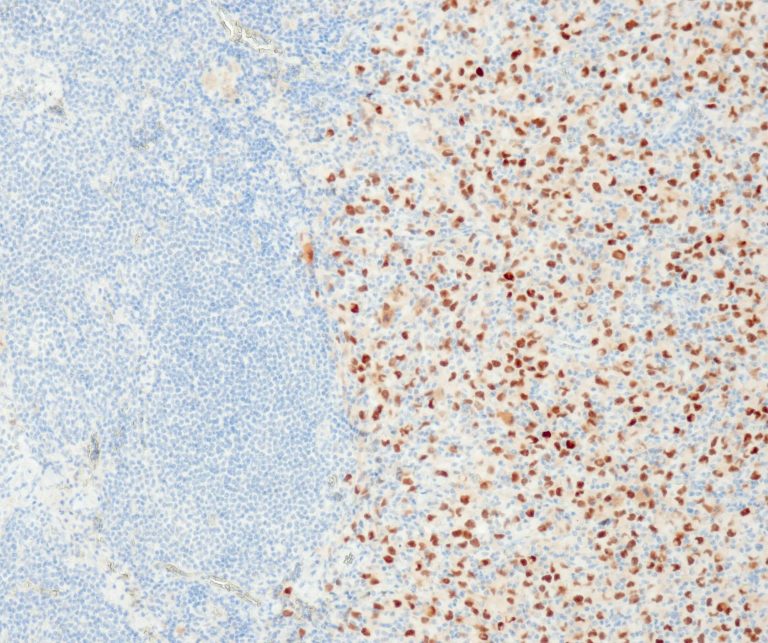

Hematopathology